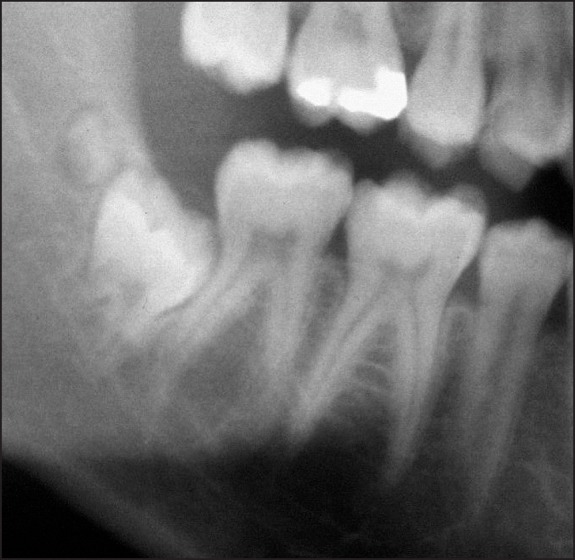

Material and methods: The panoramic radiographs of 179 patients were analysed for supernumerary molars and dysplastic wisdom teeth with special reference to facial tumour type. The results were compared to radiographic findings obtained in panoramic radiographs of age- and sex-matched controls.

Results: The total number of dysplastic or supernumerary molars was 21 (17 individuals, 4.75%) and predominantly a finding of the maxilla (maxilla: 15, mandible: 1, maxilla and mandible: 1). Differences of dental findings between neurofibromatosis type 1 (NF1) patients (n = 15) and the control group (n = 2) were statistically significant (P < 0.01). All individuals with supernumerary molars were diagnosed as being affected with NF1. This difference achieved statistical significance when it was considered that the event may occur at least once per quadrant, and thus the individual potentially needs to be considered four times (P = 0.0038).

Conclusions: This investigation revealed that supernumerary molars and aberrations in wisdom tooth form are more common in patients than in age- and sex-matched controls. There is no association between these findings and a specific feature of the disease, id est facial manifestation of a trigeminal nerve sheath tumour (plexiform neurofibroma). The cause of this phenomenon is unknown. A review of these dental findings on other neurofibromatosis type 1 study groups should be attempted.